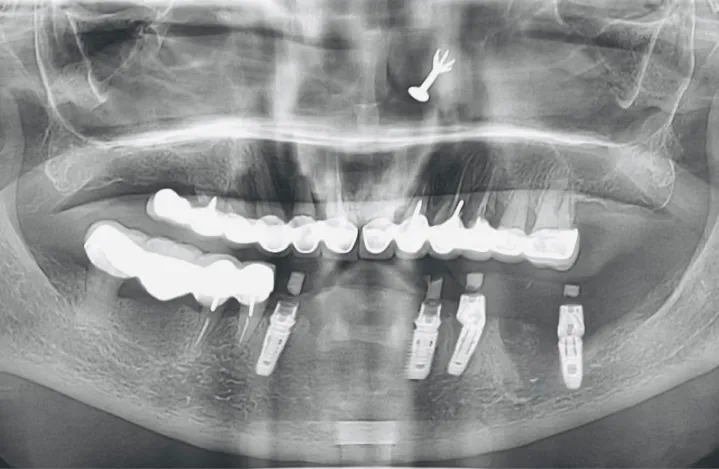

Accuracy, detail, and safety are at the forefront of our in-house CBCT and 3D dental imaging services. Single, full-arch or targeted scans provide precise, three-dimensional views of teeth, jawbone, and surrounding structures for effective diagnosis and treatment planning.

At iCube Dental, we use state-of-the-art CBCT and 3D imaging technology to ensure detailed, comfortable, and efficient scans. Our imaging services help dentists plan treatments with unmatched precision – enhancing outcomes for implants, orthodontics and complex restorations while keeping patient care safe and confident.

In-house CBCT and 3D imaging capture accurate, detailed views of your teeth, jaw, and gums, enabling precise diagnosis and treatment planning.

Advanced 3D scans reveal hidden dental issues, helping dentists plan treatments with accuracy and ensuring your smile and oral health are fully optimised.

Advanced in-house CBCT scans and 3D dental imaging at iCube Dental provide highly accurate, detailed views of teeth, jaws, and surrounding structures, supporting precise diagnosis and treatment planning.

Our state-of-the-art 3D imaging captures complete dental anatomy with minimal radiation exposure, allowing dentists to plan implants, orthodontics, and complex restorations with unmatched precision. In-house CBCT and 3D scans at iCube Dental enhance patient safety, optimize treatment outcomes, and provide a comprehensive view of oral health for confident, effective care.